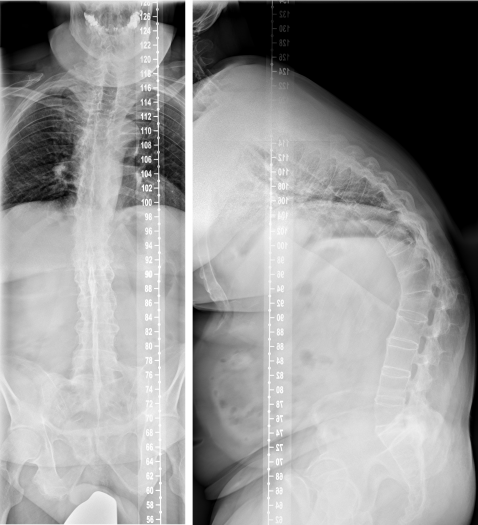

The whole spine conventional X-rays in two planes revealed an ossification of the spine, reduced bone mineral density, a global kyphotic deformity with a sagittal imbalance and the kyphotic healed fracture at the level L1 (Figure 1 [Fig. 1]). The CT scan showed the typical complete ossification of the spine and the described kyphotic deformity (Figure 2 [Fig. 2]). The DEXA measurement showed a pronounced osteoporosis.

Figure 1: Conventional X-rays of the whole spine in two planes in standing position (ap-view left and lateral view right) revealing the ossification and the kyphotic deformity of the whole spine with sagittal imbalance as well as the reduced bone mineral density.